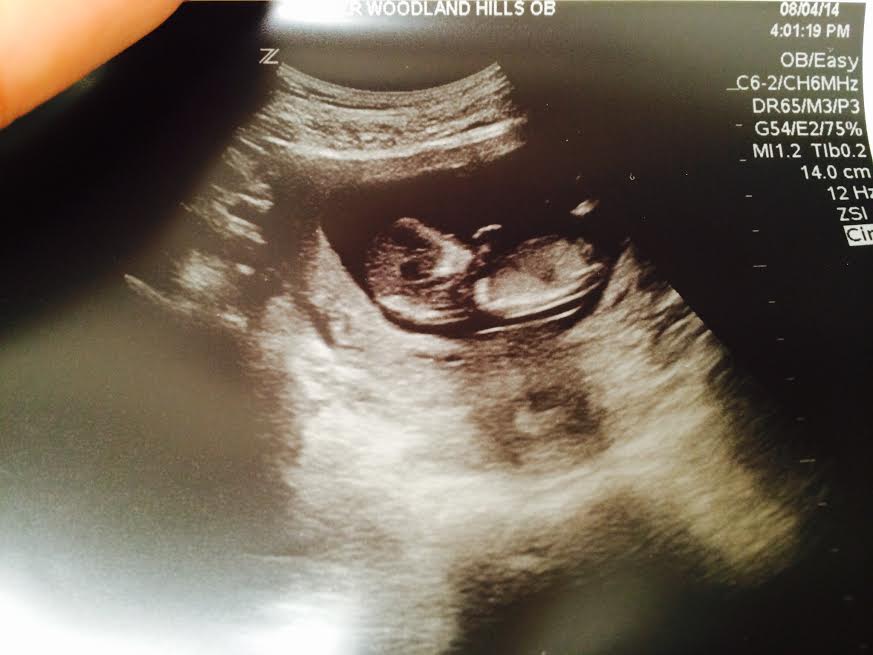

how far along: 22 weeks, 2 days

gender: a little miss!!